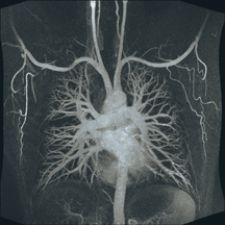

Cardiac MR Proves Effective Over Other Imaging Options

3.0 T MR is being used in the cardiac imaging arena, but there is hope that the advantages of it’s improved SNR will be truly realized down the road. There is a current disadvantage of 3.0 T cardiac imaging when it comes to greater susceptibility artifacts, but research is being conducted to work out the kinks, and should be completed within the next couple of years. While radiologists wait for 3.0 T to clearly overtake 1.5 T, cardiac MR still has advantages over other cardiac imaging options such as echocardiography, nuclear medicine and computed tomography (CT).

“MR is a very flexible technology,” stated Warren J. Manning, M.D., professor of Medicine and Radiology, Harvard Medical School and section chief of Noninvasive Cardiac Imaging at Beth Israel Deaconess Medical Center. “The sort of bread and butter of MR is it is widely recognized as the most accurate technique for assessing the size and contractility of the heart, the size and contractility of the left and right ventricle and the atria.”

Compared to echocardiography, MR has enhanced definition of the borders of the chambers. About 15 percent of the time, all the walls of the ventricle cannot be seen with echocardiography, as opposed to being able to locate endocardial borders with MR 98 percent of the time. According to Dr. Manning, MR is far more quantitative than echocardiography with regard to the size of the ventricles.

Nuclear medicine is very good for perfusion and looking for global systolic function. However, MR can identify much smaller infarctions because of the spatial resolution advantage that it holds over nuclear medicine.

“MR doesn’t use radioactive tracers and gives us information about valvular heart disease in the right ventricle, which is not assessed by nuclear medicine,” added Dr. Manning.

The major benefit of cardiac CT over MR is that it is easier to implement and for physicians to train on, but it is not as flexible. CT’s technology for imaging the coronary arteries is also more developed. It is faster and easier, but at the current time, the accuracy for each is about the same. The quicker and easier acquisition from CT does come at a price however. Unlike MR, it exposes patients to a considerable amount of radiation and ionated contrast with the risk of renal toxicity and allergic reaction.